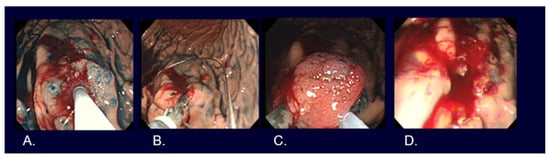

5. Types of Endoscopic Resection for Early Gastric Cancer